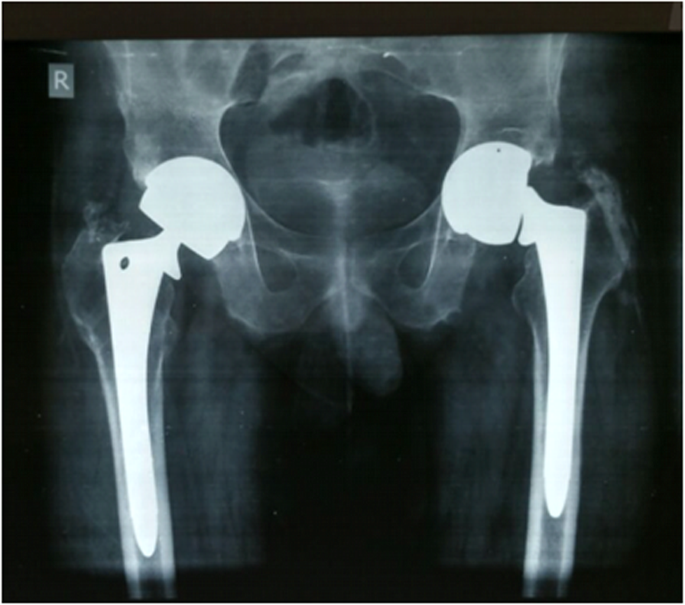

He subsequently underwent revision left THA. Both the femoral and acetabular components were revised. Intraoperatively, we found evidence of fretting corrosion at the fracture site (Fig. 2a, b). The trunnion fracture was oblique in pattern and extended superolaterally to inferomedially, exactly at the head-neck articulation. It suggested a stress riser effect and cyclic fatigue failure. The proximal part of the broken trunnion was still attached to the femoral head. We also found evidence of localized metallosis and soft tissue reaction. The femoral component was extracted by means of an extended trochanteric osteotomy and revised to a long cementless Wagner SL stem (size 14, Zimmer, Warsaw, USA). The acetabular component was extracted using an explant device and was revised to an uncemented continuum multi-hole cup (size 54 mm, Zimmer, Warsaw, USA) along with a Delta ceramic head (size 36 mm; + 7), UHMWPE liner (54 mm/36 mm), and acetabular screws. In addition, the postero-superior defect of the acetabulum was reconstructed using a Tantalum augment (size 54; thickness 15 mm). Following surgery, the patient had an uneventful recovery. Post-operative radiographs showed satisfactory alignment of the components (Fig. 3a, b). He continued to have a good functional outcome after 3 years, and the radiographs at the last follow up were as shown in Fig. 4a, b.